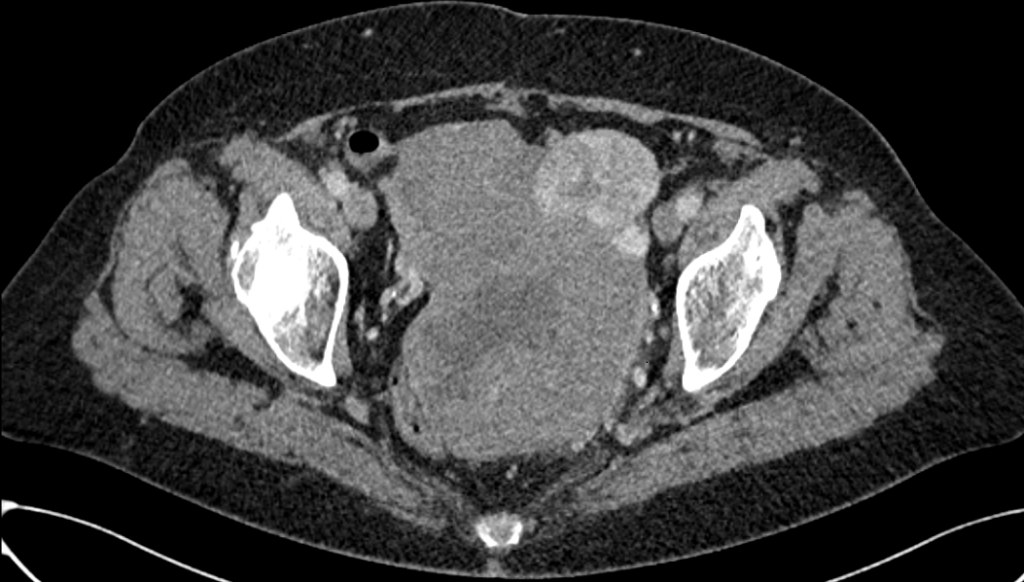

CT van het abdomen.

Een 71-jarige vrouw heeft pijn in de onderbuik en sinds kort voelt zij een zwelling in de linker lies. Soms heeft ze hevige mictieaandrang, maar de mictie komt moeizaam op gang. De CEA-waarde is laag, die van CA-125 licht verhoogd.